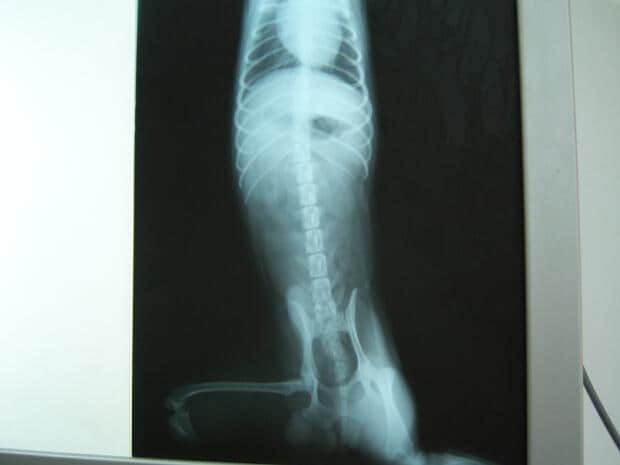

2.2 X光检查:见下图

正位:脾区异常肿大影像

由于致敏的红细胞在脾脏内淤积和大量崩解,导致脾脏肿大。